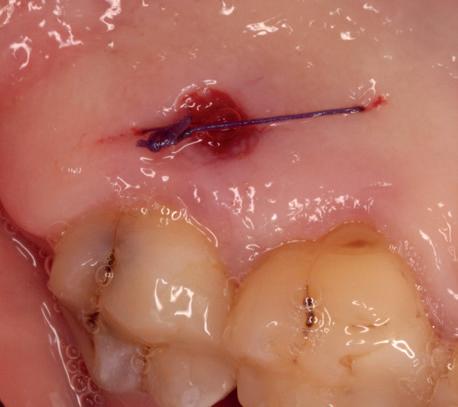

In deze casus is extractie van de 37 geïndiceerd in verband met een fistel en restpockets, zoals zichtbaar op de röntgenfoto’s (afbeelding 1). Duidelijk te zien is de forse peri-apicale ontsteking en het botverlies bij de 37, dat zowel richting buccaal als linguaal doorloopt. De 37 wordt atraumatisch verwijderd. Er is aan de linguale zijde veel bot verloren en er is sprake van een perforatie aan de buccale zijde.

Er wordt besloten om botmateriaal te plaatsen in de extractie-alveole. Vervolgens wordt het afgesloten met een titanium versterkt d-PTFE membraan (afbeelding 2). Na vier weken wordt het membraan verwijderd.